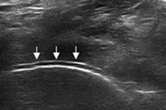

二、清晰显示软骨表面尿酸盐结晶沉积状况 判断痛风所属病期

肌骨超声可通过高清影像图判定软骨表面有无出现一条与强回声骨皮质平行的线样强回声,即“双轨征”这一痛风性关节炎特征性表现,判定疾病所属。当尿酸盐粘附并沉积于漂浮的滑膜上时,超声检查可在关节腔内发现漂浮的高亮回声;而当尿酸盐长期沉积于韧带上时,在超声中即显示条带状的略高回声(韧带)中出现高回声点、高回声带或高回声团块(尿酸盐),从而判断痛风病情处于哪一时期。

“双轨征”

跖趾关节软骨表面可见高回声不规则增强的软骨滑膜边缘线,呈“双轨征”。

高回声带

软骨表面回声增强,与深面的骨性关节面强回声线形成“双轨征”。

聚集体

髁软骨的双轨征状,显示髌腱内部的聚集体